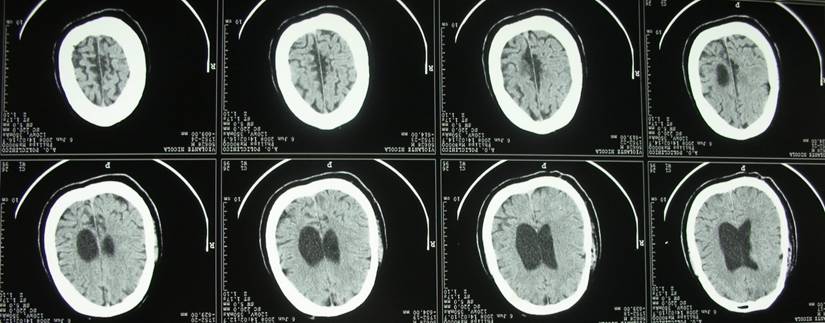

In order to achieve diagnostic certainty, we performed Computed Tomography (CT) in the emergency setting, Nuclear magnetic resonance (NMR) of the brain and Magnetic Resonance Angiography of intracranial vessels. (Figs. 3,4,5)

Fig 4

Computed Tomography

Int J Med Sci Image

Computed Tomography revealed the presence of mild dilatation of the ventricular system, and we noted parenchymal, likely vascular involvement in the right capsulolenticular area and bilateral dilatation of the cerebral cortical sulci.